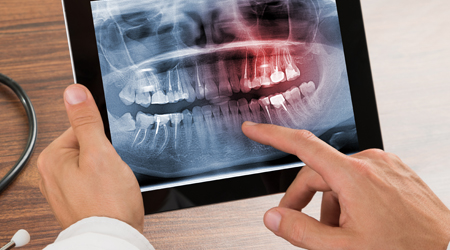

OPG (Full Mouth X-Ray) 500 10

Upload Your RVG , OPG Reports